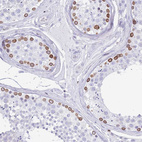

Immunohistochemistry analysis in human lymph node and skeletal muscle tissues using HPA049840 antibody. Corresponding LBR RNA-seq data are presented for the same tissues.